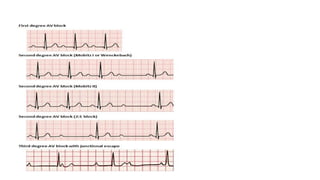

MANAGEMENTS OF BRADYCARDIA – NOTE

• Sinus bradycardia (1st line Mg., atropine 1mg)

• First degree AVB (1st line Mg., atropine 1mg)

• Second degree AVB type 1 (1st line Mg., atropine 1mg)

• Second degree AVB type 2 (2nd line Mg., may give 1

dose atropine)

• Third degree AVB (2nd line Mg., may give 1 dose

atropine)